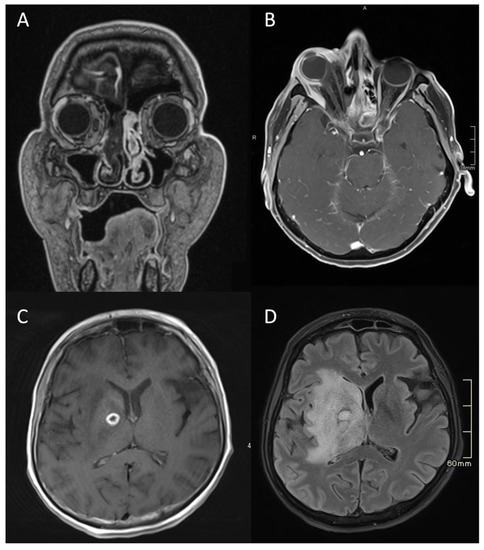

Figure 4.

MRI of a patient with an acute fulminant invasive fungal atypical skull-base osteomyelitis due to rhino-orbital-cerebral mucormycosis. (A) First coronal CE MRI T1 showing a lack of a contrast enhancement in the right nasal cavity and paranasal sinuses, indicating necrosis in the context of invasive mucormycotic infection (i.e., black turbinate sign). (B) Axial CE MRI T1 FS two weeks later, showing significant right-sided proptosis, signs of increased intra-orbital pressure, a lack of enhancement in the lateral and partially in the medial rectus muscle, and enhancing and non-enhancing parts of the eye bulb—signs of inflammation and necrosis. (C) Axial CE MRI T1 showing an abscess, which is a ring-enhancing lesion in the brain, with signs of restricted diffusion on DWI (not shown). (D) Axial flair MRI showing extensive oedema and abscess in the deep structures of the right hemisphere three months later. MRI: magnetic resonance imaging; CE: contrast-enhanced; FS: fat-saturation; DWI: diffusion-weighted imaging.

Typical for ASBO is symmetric pre-clival soft tissue involvement, producing nasopharyngeal swelling (Figure 2D,E). In addition, invasive sinus infections have a predilection for spread in the pterygopalatine fossa (Figure 3C,D) [4]. The infection of bone marrow in ASBO results in a loss of normal fat signal, which is seen as T1 hypo-intensity (Figure 2B) and STIR hyperintensity, with heterogenous contrast enhancement of the affected marrow [43,44]. Peripheral contrast enhancement is seen when an abscess is formed in the necrotic part of the bone marrow (Figure 2F,H,I). A combination of abnormal enhancement and absence of contrast enhancement is observed, particularly in mucormycotic infection, indicating the presence of inflammation and necrosis (Figure 4A,B) [45].

Imaging studies, both MRI and CT, including CTA and CTV, are essential in diagnosing complications of SBO. These include the intracranial spread of infection, the formation of an abscess, either intracranially (Figure 1B,D and Figure 4C,D) or in the soft tissues of the head and neck (Figure 2F,H,I), and vascular complications—venous thrombosis, venous or arterial stroke, and mycotic aneurism formation [30,46,47].